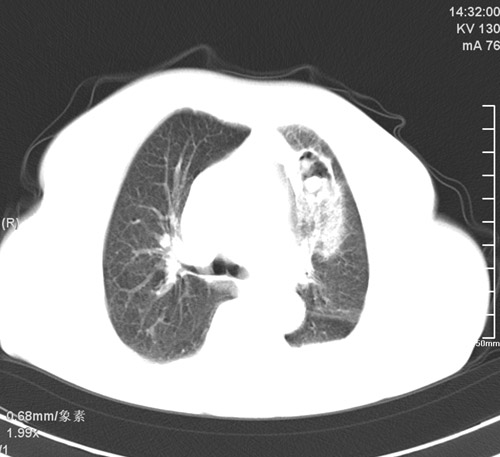

以下是引用杀毒软件在2009-4-22 18:45:00的发言:[br]考虑----左肺感染性病变〔真菌可能性大〕-----建议痰检。